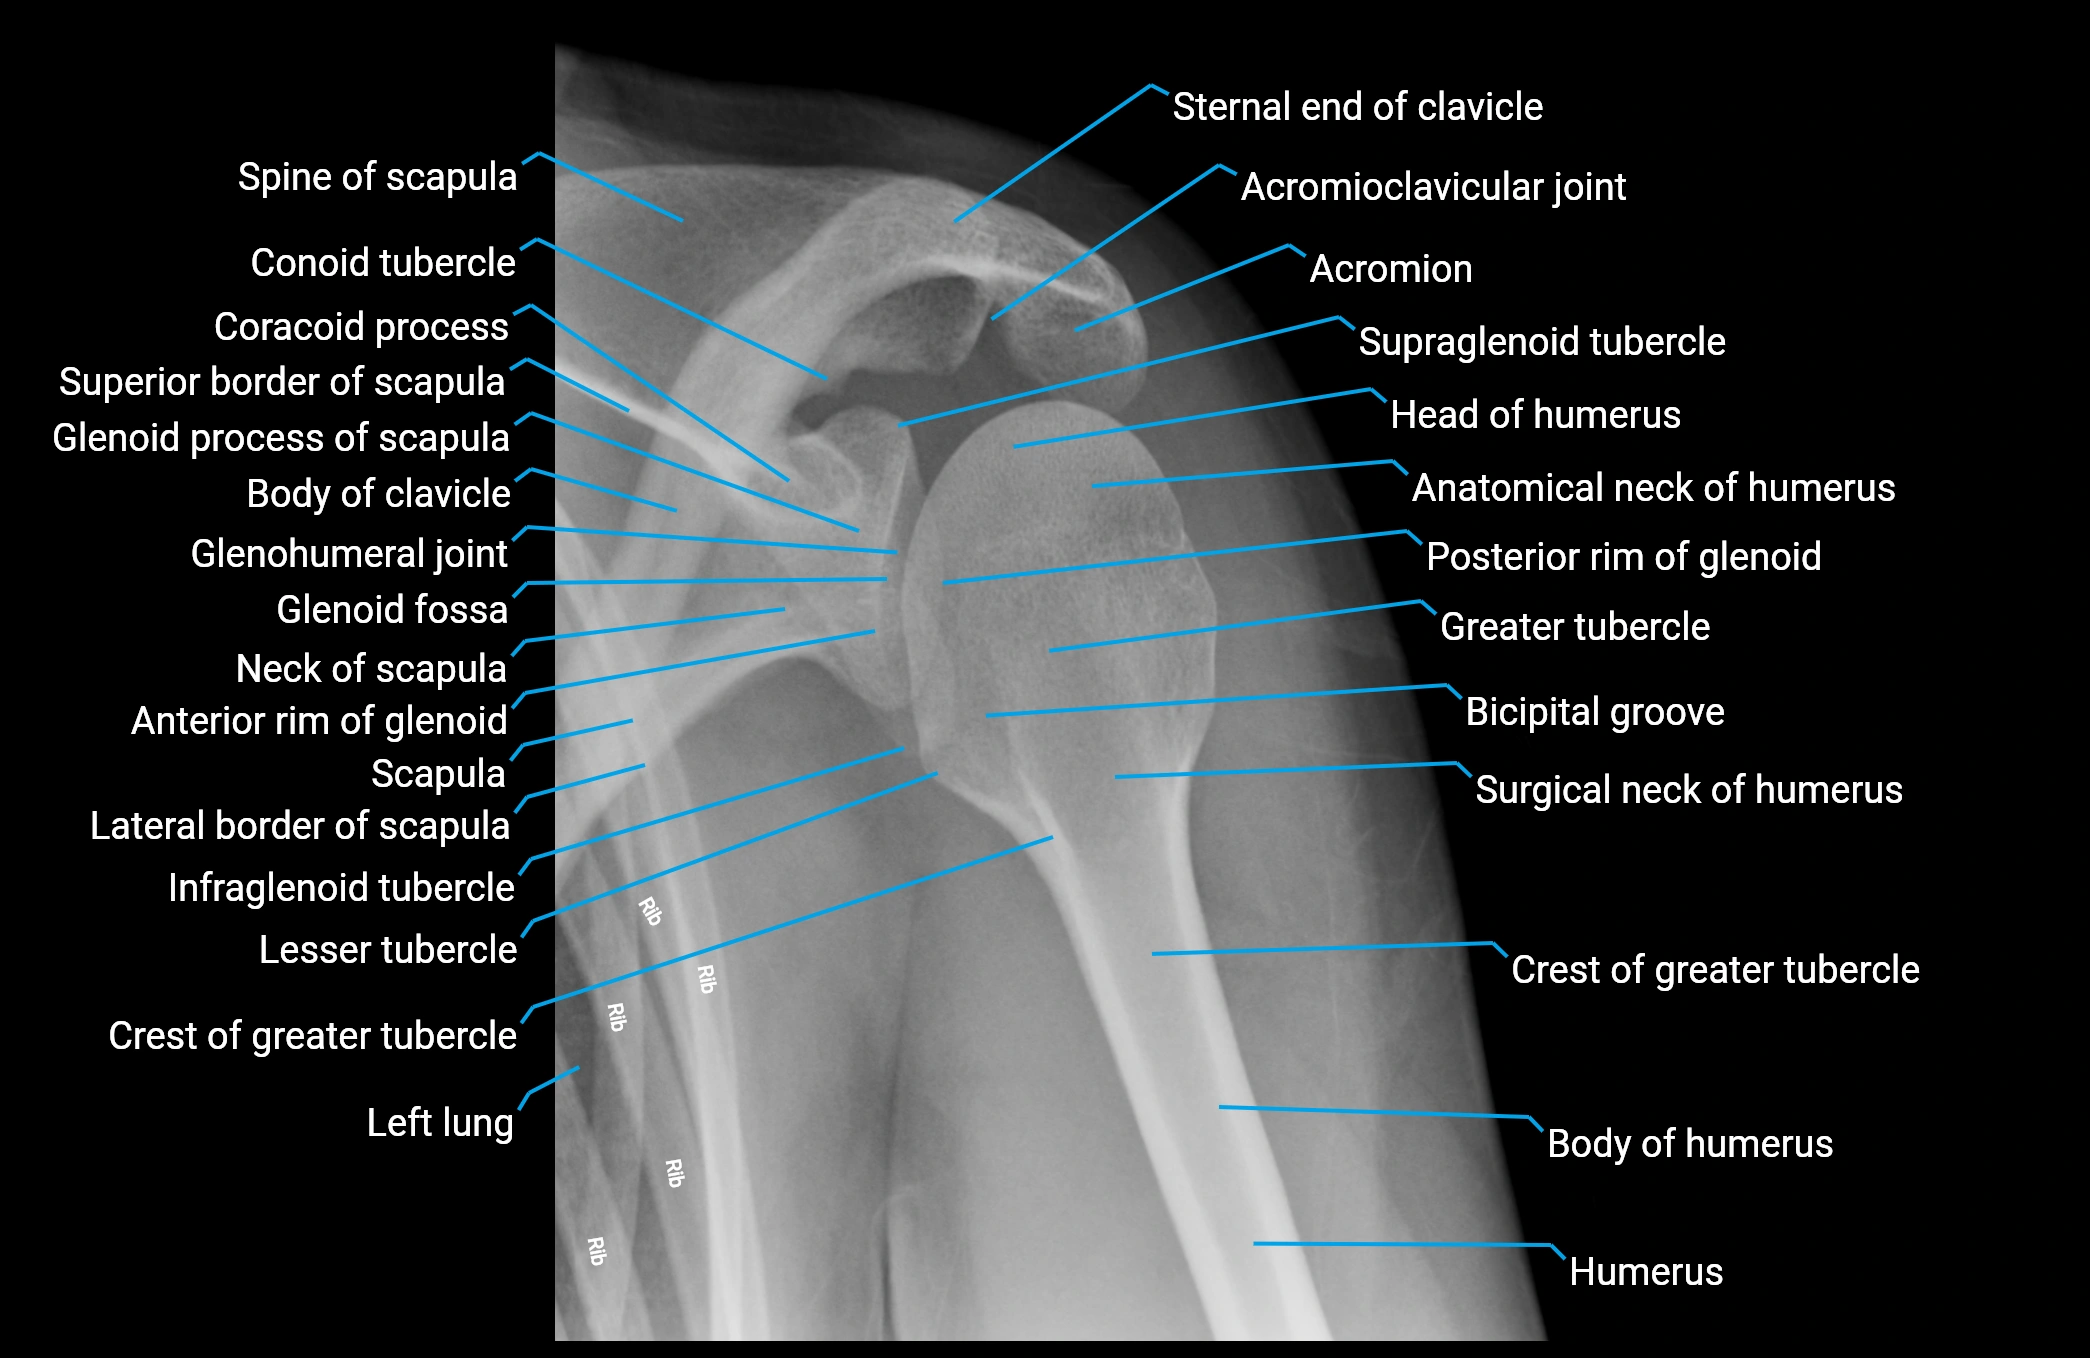

The acromial end of the clavicle is the flattened lateral extremity of the clavicle that articulates with the acromion of the scapula to form the acromioclavicular (AC) joint. Unlike the sternal end, the acromial end is broad and compressed. Its articular surface is oval, directed downward and medially, and covered with fibrocartilage.

The AC joint is stabilized by the acromioclavicular ligaments (superior and inferior) and reinforced by the coracoclavicular ligaments (conoid and trapezoid), which prevent vertical displacement. Small intra-articular fibrocartilaginous discs may be present.

This region is highly mobile, allowing scapular rotation, gliding, and elevation, which are essential for full shoulder motion. It is clinically significant as a frequent site of degeneration, separation injuries, fractures, and osteoarthritis.